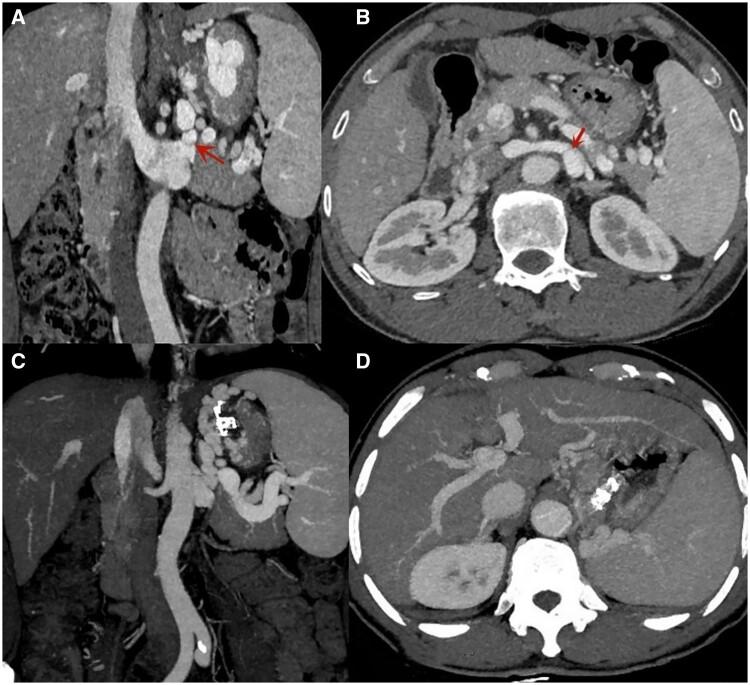

Gastric varices (GV) with spontaneous portosystemic shunts (SPSS) pose considerable risks and challenges for administering endoscopic cyanoacrylate (CYA) injection. This study aimed to evaluate the efficacy and safety of EUS-guided coil embolization in combination with CYA injection compared to conventional endoscopic CYA injection for managing GV with SPSS.

This retrospective analysis included patients with SPSS treated with either EUS-guided coil embolization in combination with CYA injection or conventional CYA injection for gastric variceal bleeding at Ningbo Medical Center Lihuili Hospital (Zhejiang, China) between January 2018 and March 2023. Patient demographics, procedural details, and follow-up results were reviewed.

The study evaluated 57 patients: 21 in the combined treatment group undergoing EUS-guided coil embolization in combination with CYA injection and 36 in the conventional group receiving conventional endoscopic CYA injection. Both cohorts achieved a 100% technical success rate. The mean volume of CYA used was significantly lower in the combined group (1.64 ± 0.67 mL) than in the conventional group (2.38 ± 0.72 mL; <0.001). Early GV rebleeding rates did not differ significantly between the groups; in contrast, the combined treatment group exhibited a considerably lower incidence of late GV rebleeding than the conventional group (4.8% 27.8%, =0.041).

EUS-guided coil embolization in combination with CYA injection demonstrated superiority over conventional endoscopic CYA injection in reducing late GV rebleeding in treating GV with SPSS.